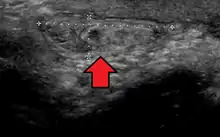

By far the most common hernias (up to 75% of all abdominal hernias) are inguinal hernias, which are further divided into the more common indirect inguinal hernia (2/3, depicted here), in which the inguinal canal is entered via a congenital weakness at its entrance (the internal inguinal ring), and the direct inguinal hernia type (1/3), where the hernia contents push through a weak spot in the back wall of the inguinal canal. An indirect inguinal hernia and a direct inguinal hernia can be distinguished by their positioning in relation to the inferior epigastric vessels. An indirect hernia is situated laterally to these vessels, whereas a direct hernia is positioned medially to them. Inguinal hernias are the most common type of hernia in both men and women. In some selected cases, they may require surgery.